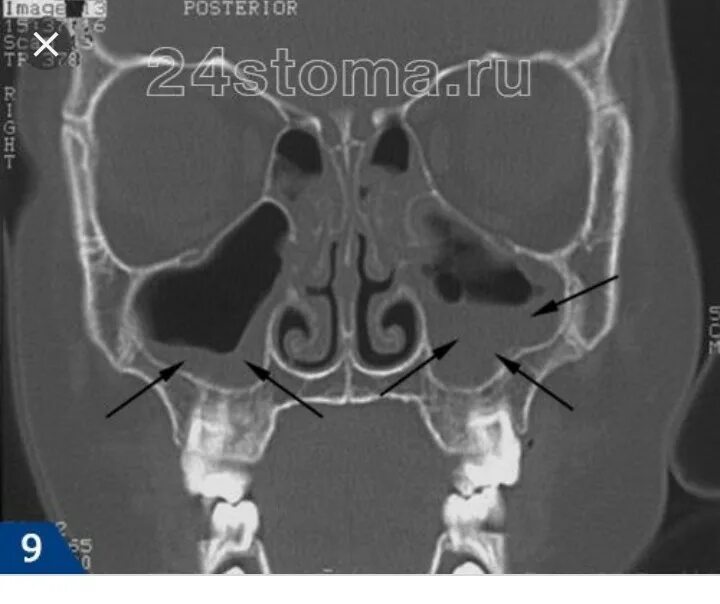

Как лечить утолщение слизистой верхнечелюстной пазухи